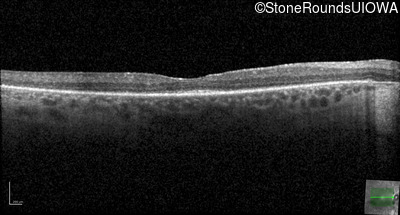

Optical Coherence Tomography - Right - 20/50 -2

Exemplar / OCT Stack